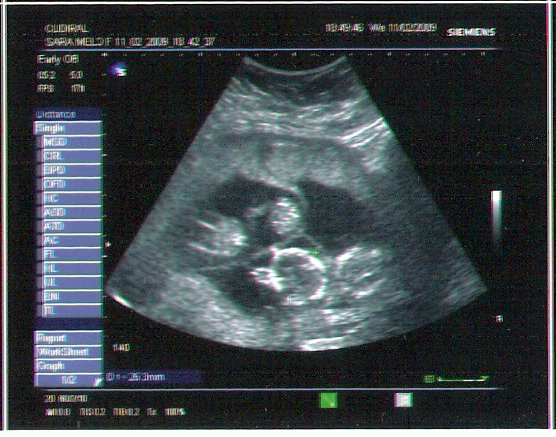

Esta é a primeira ecografia!Era dia 11 de Fevereiro de 2009 e estava de 13 semanas e 6 dias!Doutor:São dois...não,desculpe,são três...está aqui uma manchinha...oh,afinal são quatro!!!Eu:ahahahahahahahahahahahahahahah...ahihahihahihahihaihaiahaiah....veja lá se não está um quinto,assim já dá para ser uma equipa de futsal!